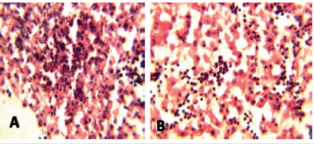

La evaluación histopatológica de las muestras mostró diversos grados de picnosis y cariorrexis (A), y cuerpos de inclusión intranucleares con marginación de la cromatina

(B) (Figura 2). También se presentaron múltiples hemorragias subcapsulares, grupos multifocales de hepatocitos y degeneración lipídica.

Figura 2. Histopatologia de hígados